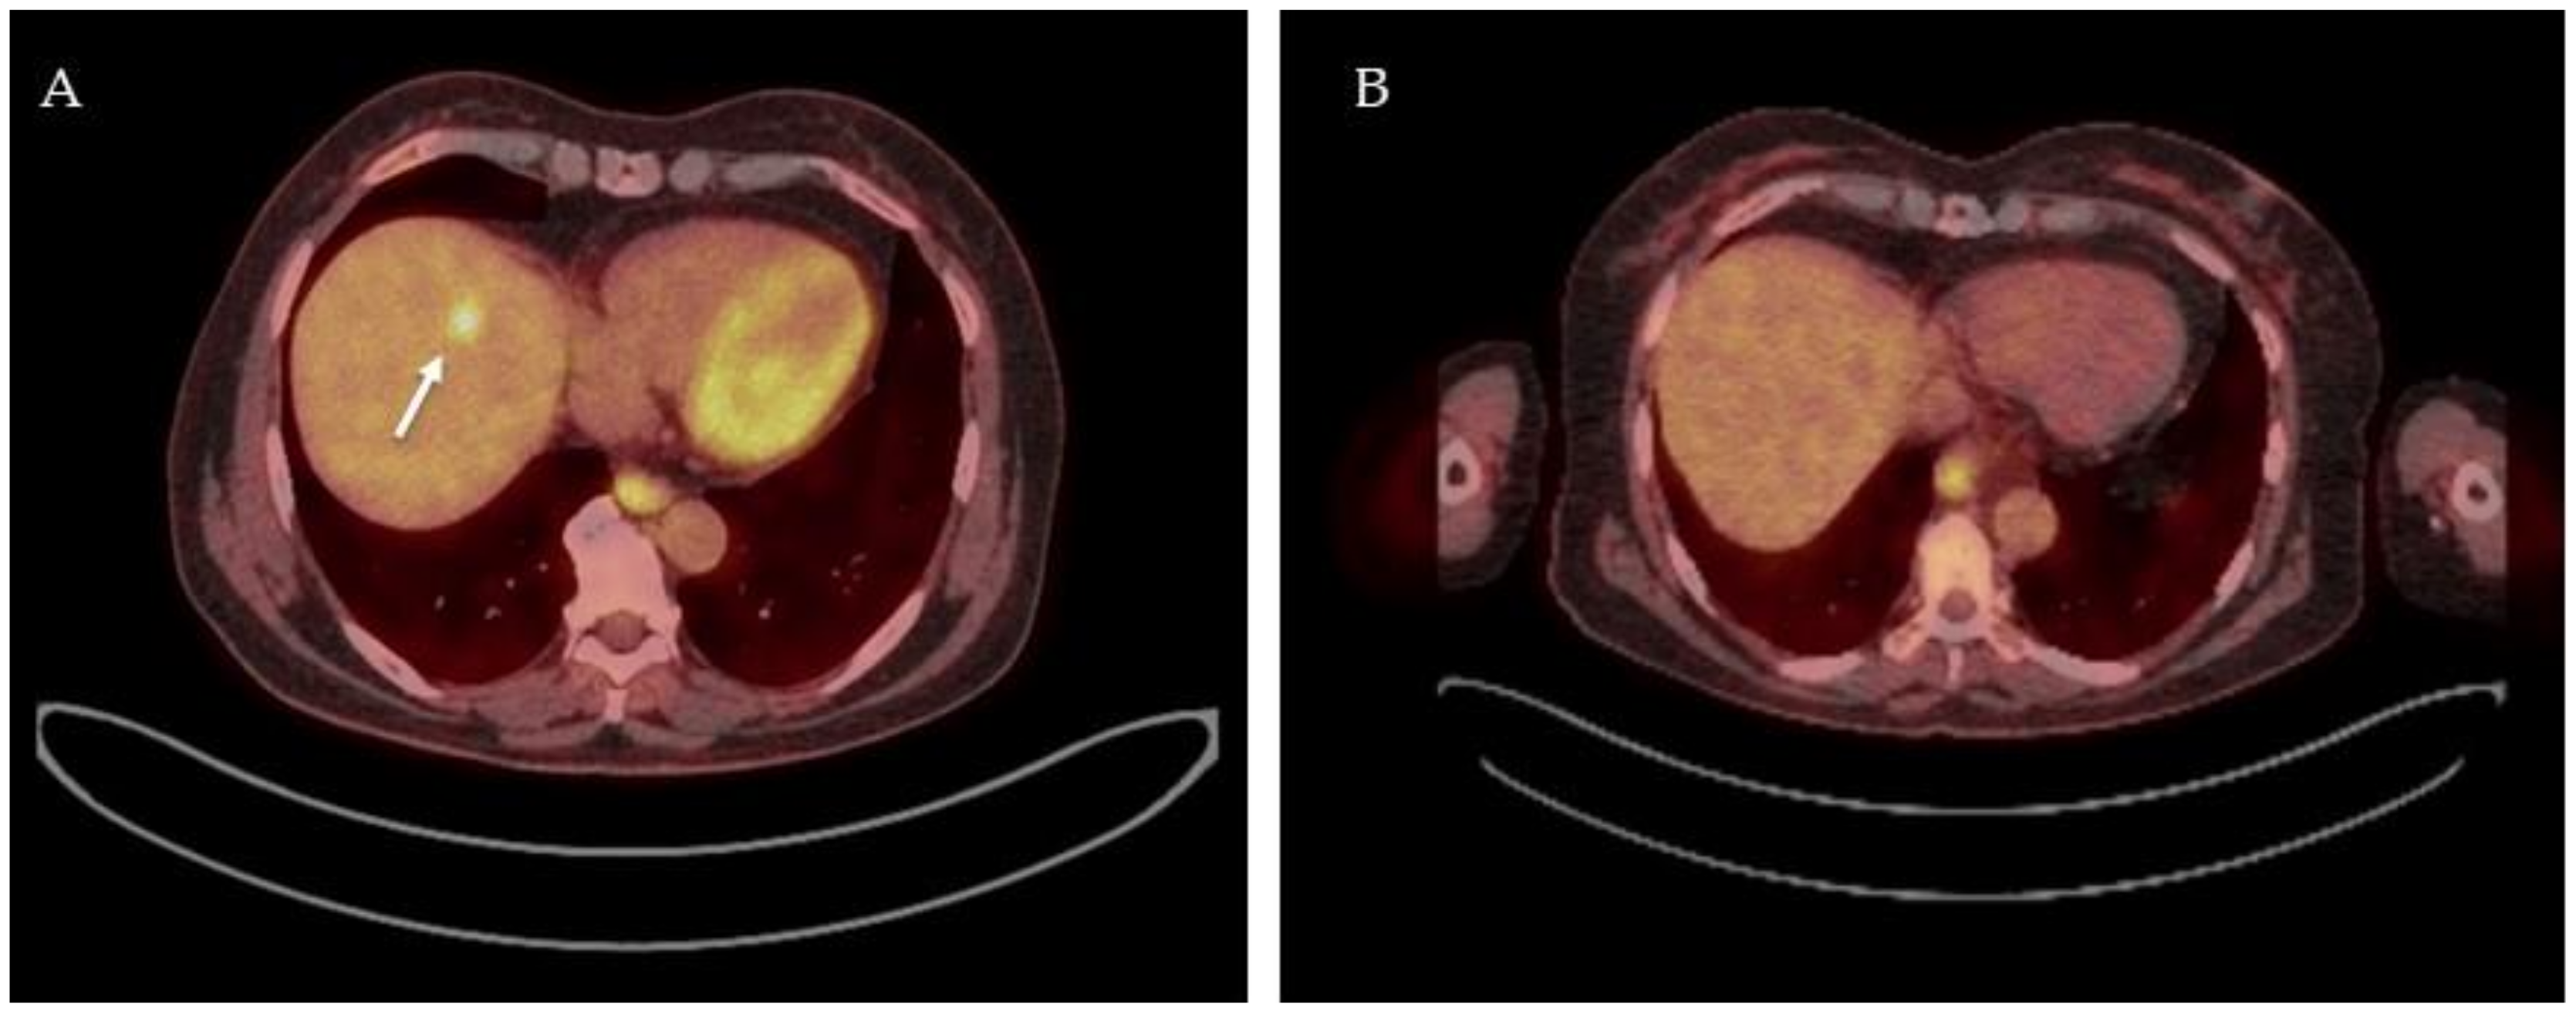

The analyzed studies used different treatment regimes, imaging timepoints, and assessment criteria. Three studies assessed metabolic response on 18F-FDG-PET-CT using SUVmean, SUVmax, and ΔSUV as predictors of pathologic response and concluded poor-to-moderate predictive performance. Multiple parameters such as SUVmax, MTV, and TLG seem to have a predictive value on patient outcomes and could be used as a prognostic marker for the prediction of long-term outcomes in CRLM treated by neoadjuvant chemotherapy and surgery. Accordingly, the vast majority of the evaluated articles have positive outcomes on the performance of 18F-FDG-PET-CT after neoadjuvant chemotherapy for CRLM. Typical findings on 18F-FDG-PET-CT before and after neoadjuvant therapy is displayed in Figure 3, and an overview of included studies and results is summarized in Table 3.

Figure 3.

18F-FDG PET-CT images of a patient before and after receiving neoadjuvant chemotherapy. 18F-FDG PET-CT fusion image with high focal FDG uptake in segment 4A indicative of a colorectal liver metastasis, white arrow (A); 18F-FDG PET-CT fusion image after 3 cycles of neoadjuvant chemotherapy (FOLFOXIRI-bevacuzimab) showing solely physiological FDG uptake in healthy liver parenchyma (B) indicating a complete metabolic response.